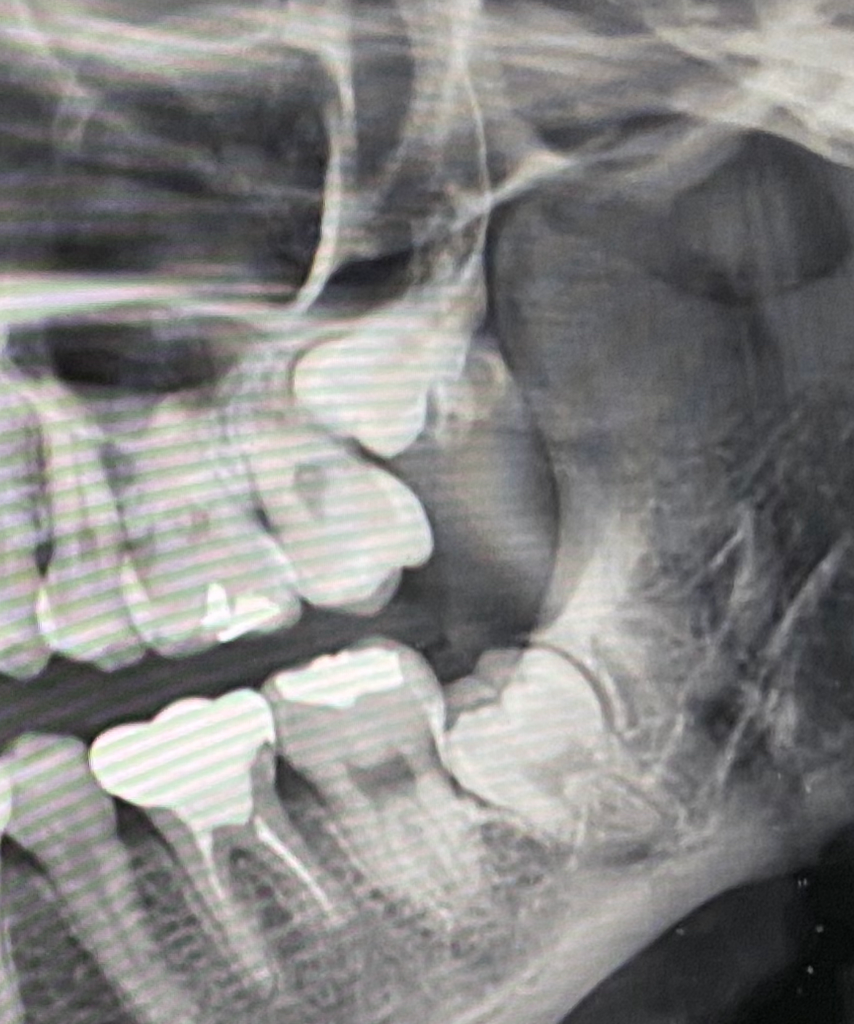

사랑니 발치 난이 어느정도 될까요?

사랑니 4개중에 2개 뽑고 2개 남았는데 난이도가 어떨까요??

둘다 완전매복이고

반대쪽 아래 뽑을때는 턱뼈에 묻혀있다해서 뽑고나서 통증과 붓기때문에 고생했는데

이쪽도 그럴까요?? ㅜㅜ

치과에서 남들보다 아래턱뼈가 짧다? 고 하셨는데 사랑니 뽑을때 문제가 되는건 아닌지 궁금합니다

아래쪽은 빼는데는 크게 어렵진 않아보이지만 오히려 위쪽이 뺄때 잇몸을 열거나 뼈삭제를 많이 해야될가능성이 높아 보이네요.

왼쪽 아래 사랑니의 경우에도 오른쪽과 마찬가지로 완전 매복 되어있어 비슷한 통증이나 붓기가 생길 것으로 보입니다

위 사랑니는 무난하지만 아래쪽은 턱이 작아 신경과 치아가 가까워 신경손상 가능성이 있습니다.